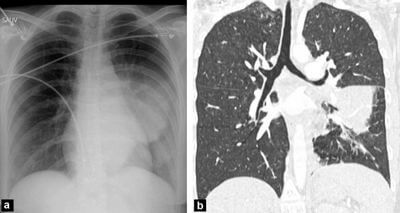

Рак легенів

КТ є найкращим тестом для діагностики раку легенів. За допомогою КТ можна виявити невеликі пухлини в легенях, які можуть бути невидимі на рентгенівському знімку грудної клітки. КТ також може допомогти визначити стадію раку і те, чи поширився він на інші частини тіла.

Пневмонія

КТ може виявити ділянки запалення в легенях, які є ознаками пневмонії. Ці сканування також можуть допомогти визначити ступінь тяжкості інфекції та найкращий курс лікування.